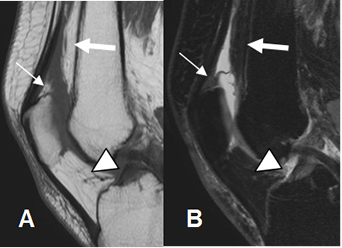

Fig 11. Mecanismo extensor normal.

A: RM sagital en T1 y B: RM sagital en T2. Tendón del cuadriceps (Flechas gruesas) y patelar (Flechas delgadas) de aspecto normal, hipointensos en ambas secuencias.

Fig 12. Mecanismo extensor normal.

RM sagital en T1. Zonas hipointensas en el tercio proximal del tercio proximal y distal del tendón patelar, por variante normal.